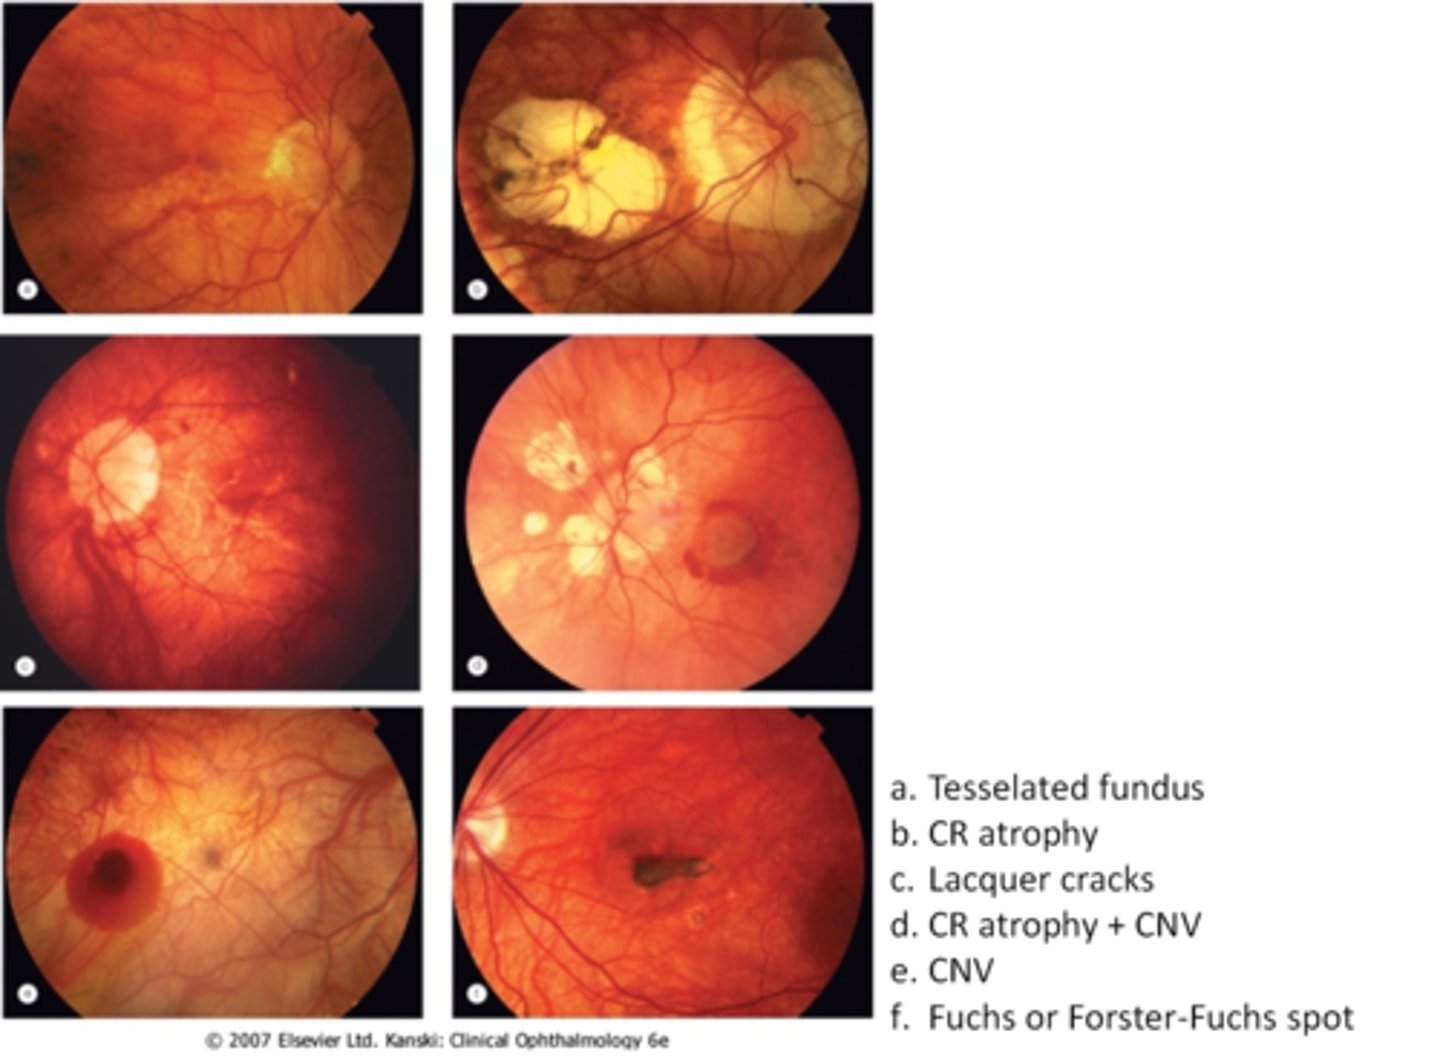

What are some common findings in high myopia?

tesselated or tigroid fundus = visibility of choroidal vasculature (A)

What are some common findings in degenerative myopia?

lattice degeneration

lacquer cracks (C)

What are 3 possible complications of degenerative myopia?

CNV (E)

chorioretinal atrophy (B)